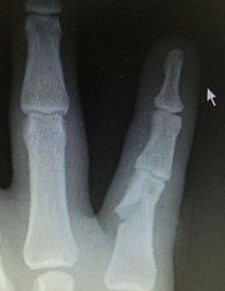

Distal falanks, parmak ucundaki kemiktir. Uygun parmak fonksiyonu ve tırnak büyümesi için sabit bir distal falanks gerekir. Çoğu distal falanks kırığının düzeltilmesi gerekmezken, bazılarının düzeltilmesi gerekir. Bunlar, düzgün bir şekilde birleştirilmesi gereken birçok parça ile oldukça karmaşık olabilir. Kötü bir şekilde düzeltilmiş kırıklar iyi iyileşmez, çok fazla ağrıya neden olur ve işe dönüşü geciktirir.

Eldeki kapalı kırıklar, yerinden oynamışsa veya deformiteye neden oluyorsa, uygun hizaya geri konulmalı ve ele iyi bir fonksiyon kazandırmak için metal teller, vidalar veya plakalarla sabitlenmelidir. Bu, el yaralanmasından birkaç gün sonra, mümkün olan en kısa sürede erken rehabilitasyona izin vermek için en iyi şekilde yapılır.